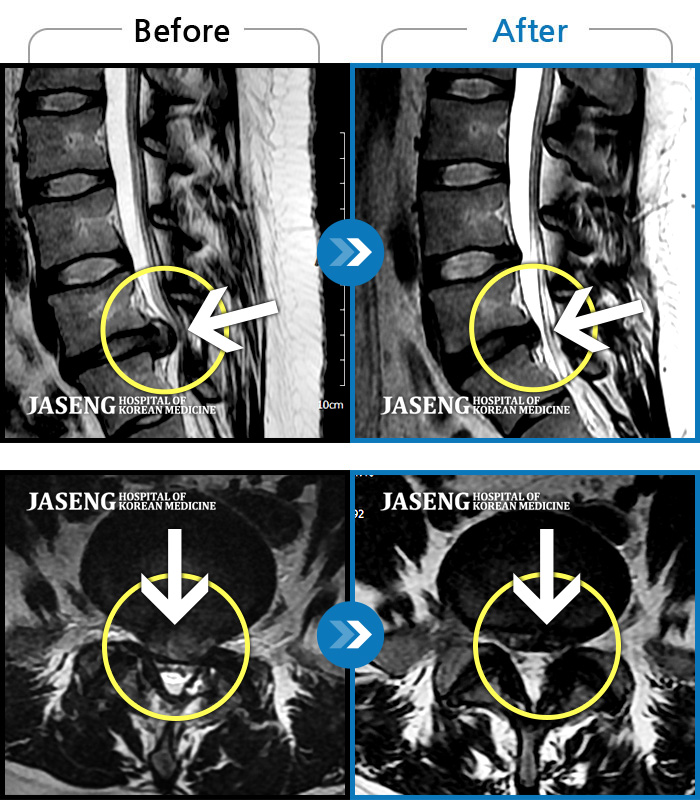

MRI ũ ʸ Ȯϼ.